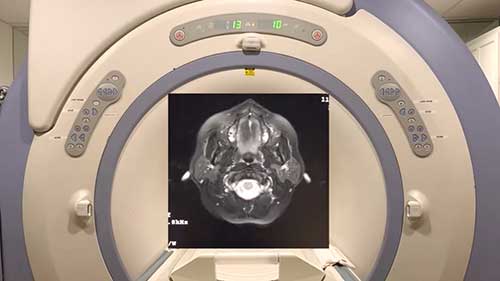

磁共振成像的原理

什么是MRI(磁共振成像)?磁共振成像的工作原理又是什么呢?

磁共振成像的工作原理

磁共振成像对医学诊断和治疗产生了极大的影响,但是很多人并不了解其工作原理。

磁共振成像仪的交付

美国托伦斯纪念医疗中心的伦德奎斯特大楼即将交付崭新的磁共振成像设备。

磁共振成像背后的知识

磁共振成像的原理是什么?磁共振成像检查需要多长时间?磁共振成像安全吗?

MRI扫描室里的声音

MRI设备在运行过程中会发出各种不同的声音,让我们来了解一下。